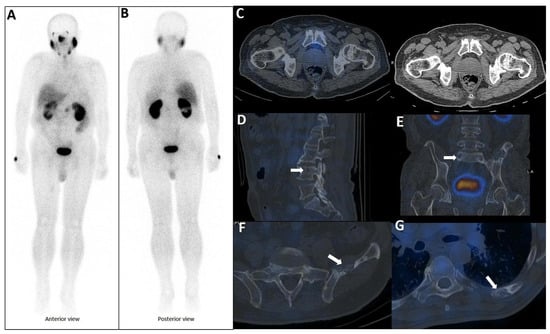

Background/Objectives: Extramedullary involvement in multiple myeloma represents an aggressive disease phenotype, associated with reduced survival and an unfavorable prognosis. Thoracic manifestations are rare and remain poorly characterized in the literature. Methods: We conducted a retrospective, single-center study at the Fundeni Clinical Institute, including patients diagnosed with multiple myeloma between February 2010 and February 2025. The study cohort consisted of 34 patients with infiltration of the pulmonary parenchyma, pleura, or the presence of myelomatous pleural effusion. Diagnosis was confirmed using a combination of imaging modalities (computed tomography or magnetic resonance imaging), cytological examination, immunophenotyping, and histopathological confirmation whenever feasible. Results: Out of a total of 2012 patients with multiple myeloma, the incidence of pleuro-pulmonary extramedullary involvement was 1.6%. The median age at diagnosis was 58 years. Pleuro-pulmonary disease was present at initial diagnosis in 26.5% of cases, while 73.5% developed it at relapse. The most common presentation involved combined pleural involvement and myelomatous effusion (70.6%). Adverse prognostic markers included elevated β2-microglobulin levels (in over 80% of cases) and increased lactate dehydrogenase (LDH) in approximately 50%. Cytogenetic abnormalities such as del(17p), t(4;14), t(14;16), t(11;14), and 1q gain were identified. The median overall survival (OS) from the diagnosis of pleuro-pulmonary extramedullary disease was 16 months, with a 2-year survival rate of 25%. No patient survived beyond 5 years. The median progression-free survival (PFS) was 9 months. Conclusions: Our findings confirm the aggressive clinical course and poor prognosis of these disease manifestations, mainly when they occur at relapse. In the absence of standardized treatment guidelines, individualizing therapy and accessing novel strategies may be essential for improving patient survival.